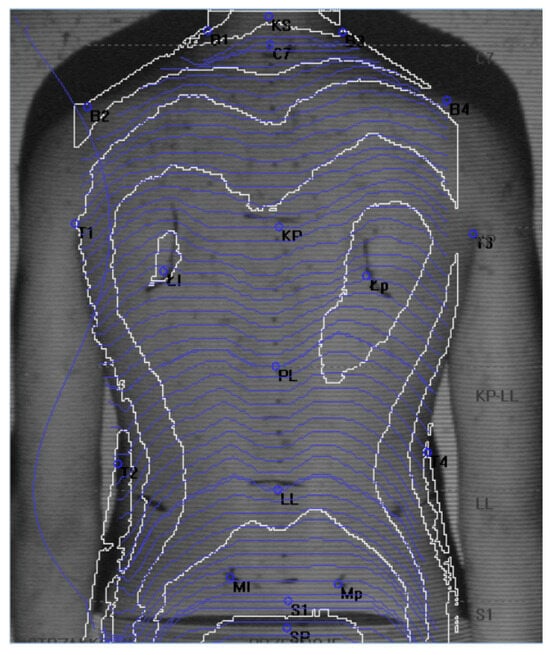

2.3. The Moiré Method

- Alpha angle—the inclination of the lumbosacral spine;

- Beta angle—the inclination of the thoracolumbar section;

- Gamma angle—the inclination of the upper thoracic spine;

- KKP—the size of kyphosis in the thoracic spine;

- KLL—the size of lordosis in the lumbar spine;

- KPT—the torso inclination angle;

- GLL—the depth of lordosis in the lumbar spine;

- UL—the difference in height between the right and left shoulder blades;

- UB—the difference in depth between the right and left shoulder blades;

- OL—the difference in the distance between the right and left shoulder blades in relation to the spine line;

- KLB—the angle of inclination of the right and left shoulder;

- TT—the difference in height of the right and left waist triangle;

- TS—the difference in width between the right and left waist triangles;

- KNM—the angle of inclination of the posterior iliac spines in the pelvis;

- KSM—the angle of twisting of the posterior iliac spines in the pelvis.

- Porto, F.; Gurgel, J.L.; Russomano, T.; Farinatti, P.d.T. Moire topography: Characteristics and clinial application. Gait Posture 2010, 32, 422–424. [Google Scholar] [CrossRef]

- Filho, J.N.S.; Batista, L.A.; Gurgel, J.L.; Porto, F. Shadow Moire technique for postural assessment: Qualitative assessment protocol by intra- and inter-rater evaluation. J. Phys. Ther. Sci. 2017, 29, 356–360. [Google Scholar] [CrossRef]

- Labecka, M.K.; Plandowska, M. Moiré topography as a screening and diagnostic tool—A systematic review. PLoS ONE 2021, 16, e0260858. [Google Scholar] [CrossRef] [PubMed]